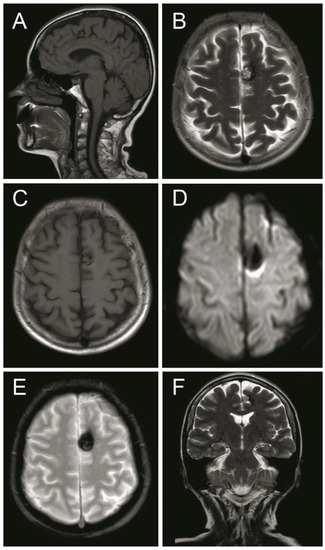

2. Case Presentation